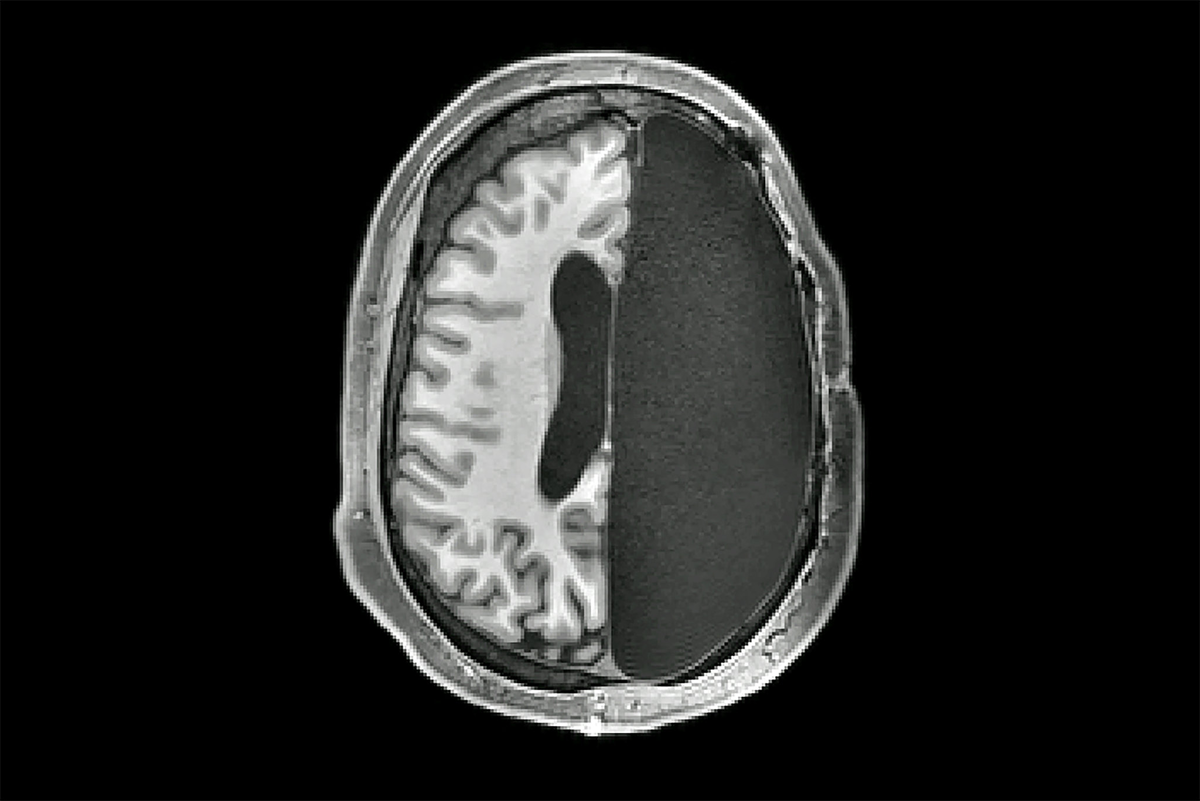

Как мозг может перестраиваться после удаления его половины

Многие специалисты, работающие на МРТ, видят пациентов, перенесших гемисферэктомию, и не могут найти никаких внешних отличий: обычный человек заходит в комнату для обследования, здоровается, ведет беседу. И только позже по результатам МРТ-сканов диагносты могут сильно удивиться.

"Каждый раз, глядя нас сканы этих пациентов, я думаю: ого, такой мозг никак не может функционировать", – делится впечатлениями нейрофизиолог из Калифорнийского института технологий. "Если взять любую другую систему, состоящую из множества функциональных единиц, связанных между собой, и удалить ее половину – она перестанет работать. Будь это сердце человека или ноутбук – результат одинаков". Но только не в случае с мозгом.